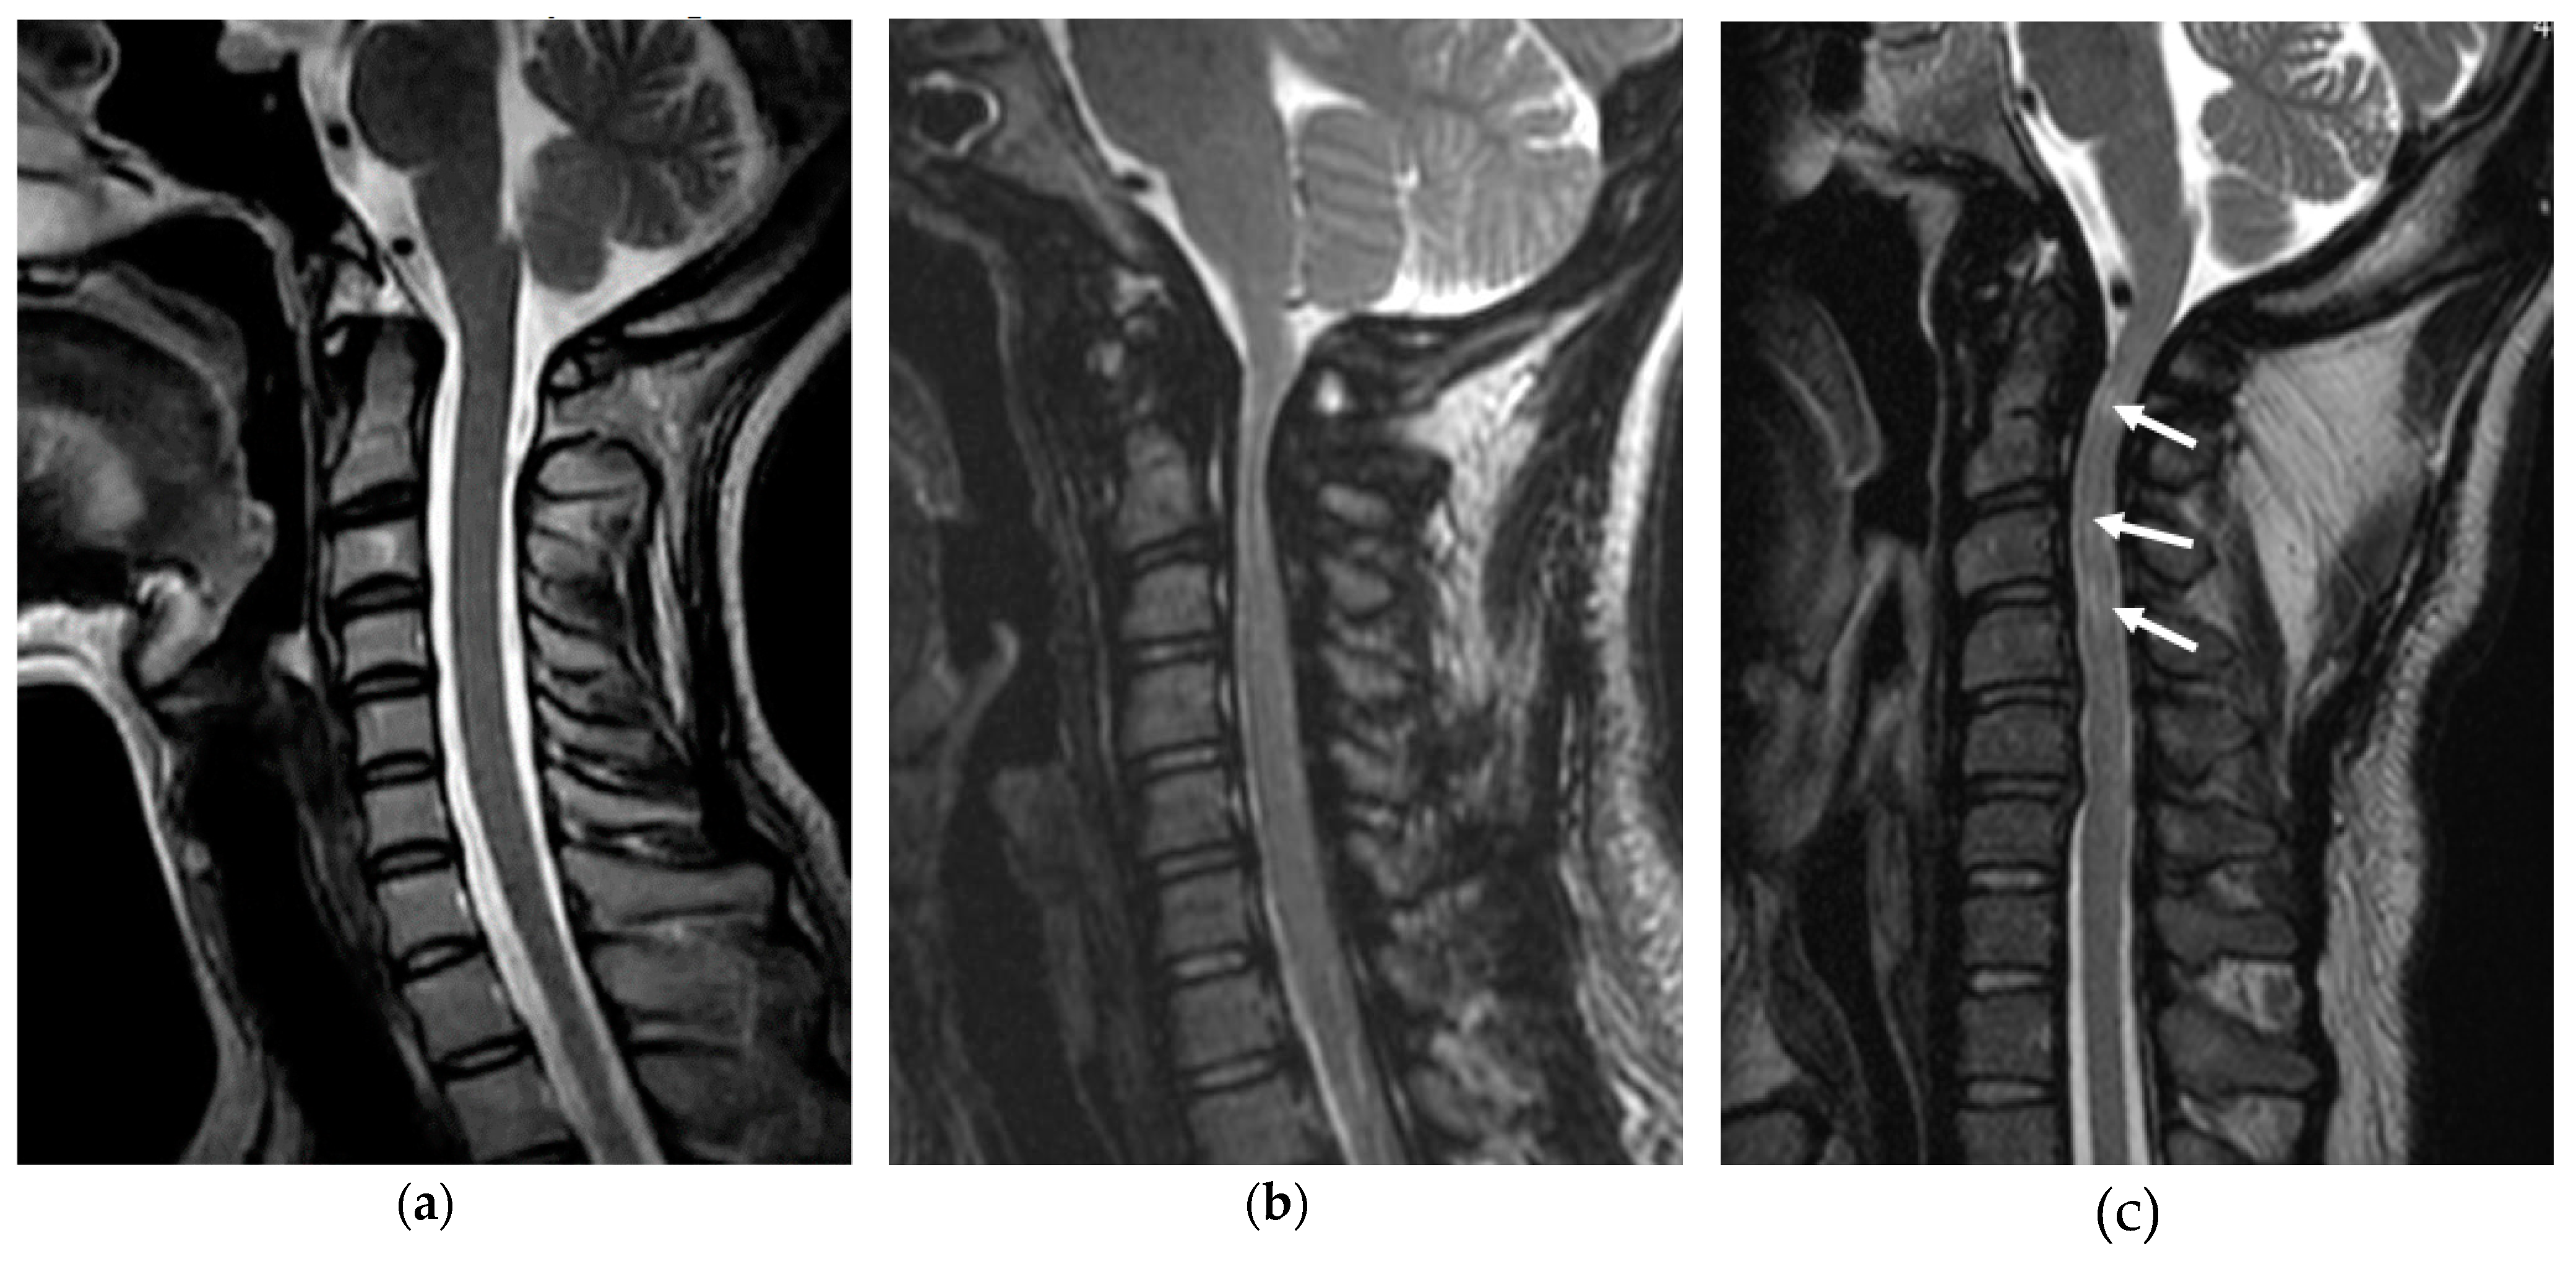

Figure 4.

Cervical stenosis in MPS. Typical sagittal T2-weighed magnetic resonance image of the cervical spine in a normal adult (a), MPS I (31-year-old woman) (b), and MPS II (37-year-old man). GAG accumulation and stenosis is evident, especially around the odontoid process. Multiple T2 high-signal-intensity changes are observed in the spinal cord (arrows). Compared with the upper thoracic levels, blocked cerebrospinal fluid flow secondary to the hypertrophied ligamentum flavum is seen (c).